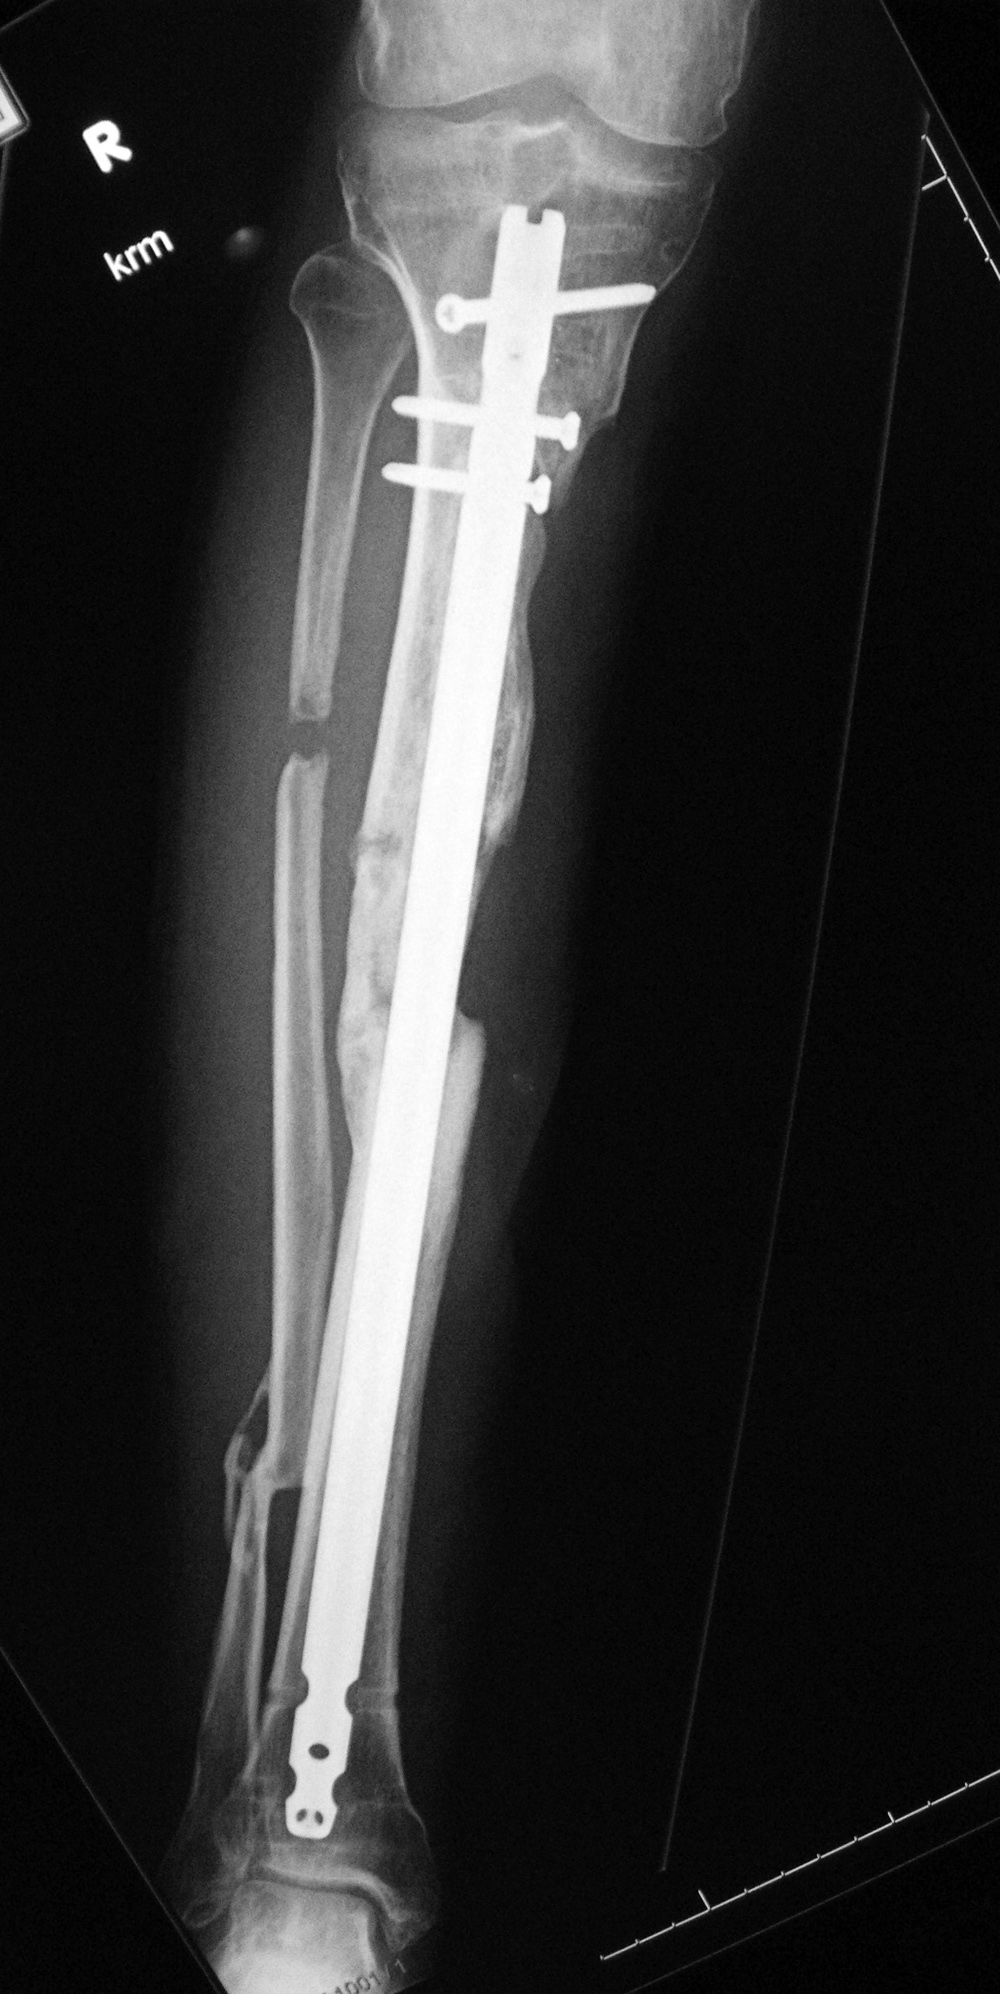

Intramedullary tibial nail and fibula Rush rod

Right tibia fracture dynamization

Right tibia dynamization - before

Right tibia dynamization - after

43 year-old man with complex, healing right tibia and fibular fractures. There is an intramedullary rod (nail) in the right tibia. Four locking screws are present proximally and two distally. After dynamization the distal locking screws have been removed.